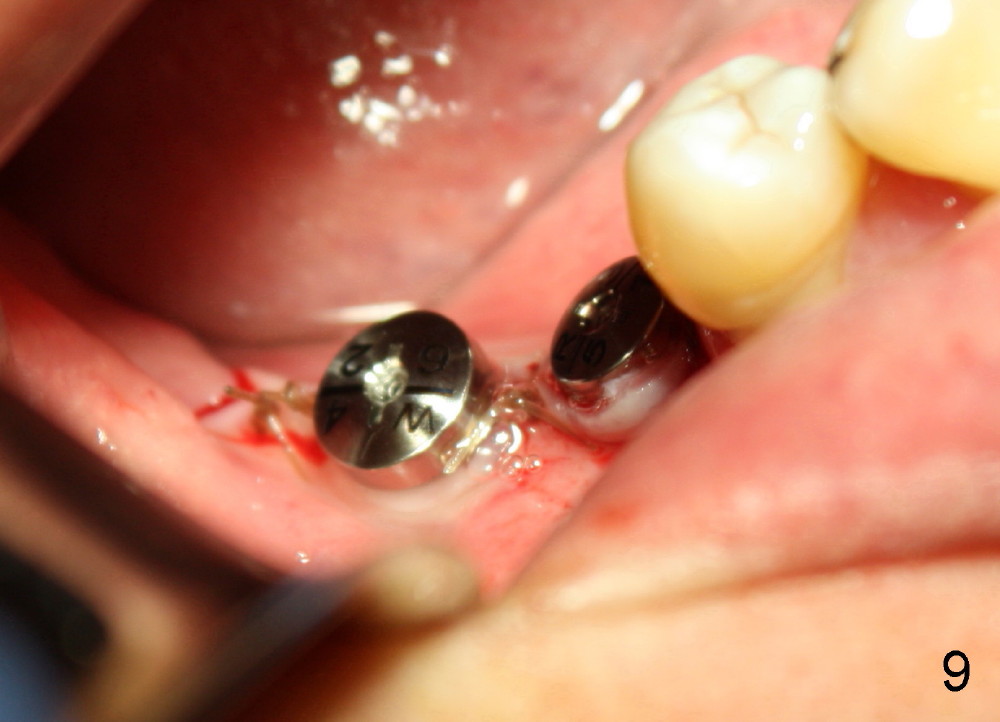

Finally 5.3x10 mm SM implant is placed at #31 (Fig.7). Healing abutments (Ɵ5.2x3(1) and 6.2x4(2) mm) are placed at #30 and 31, respectively (Fig.7-9).

One week postop, the gingiva buccal to #30 healing abutment was reddish (at the area indicated by arrowheads in Fig.10,11). The patient complained facial swelling. Clindamycin was taken one extra week to help resolve postop infection. By 24 days postop, there is no infection around these two healing abutments (Fig.10-12). The patient is pleased and makes an appointment for #18 implant placement (Fig.1), which is more challenging.